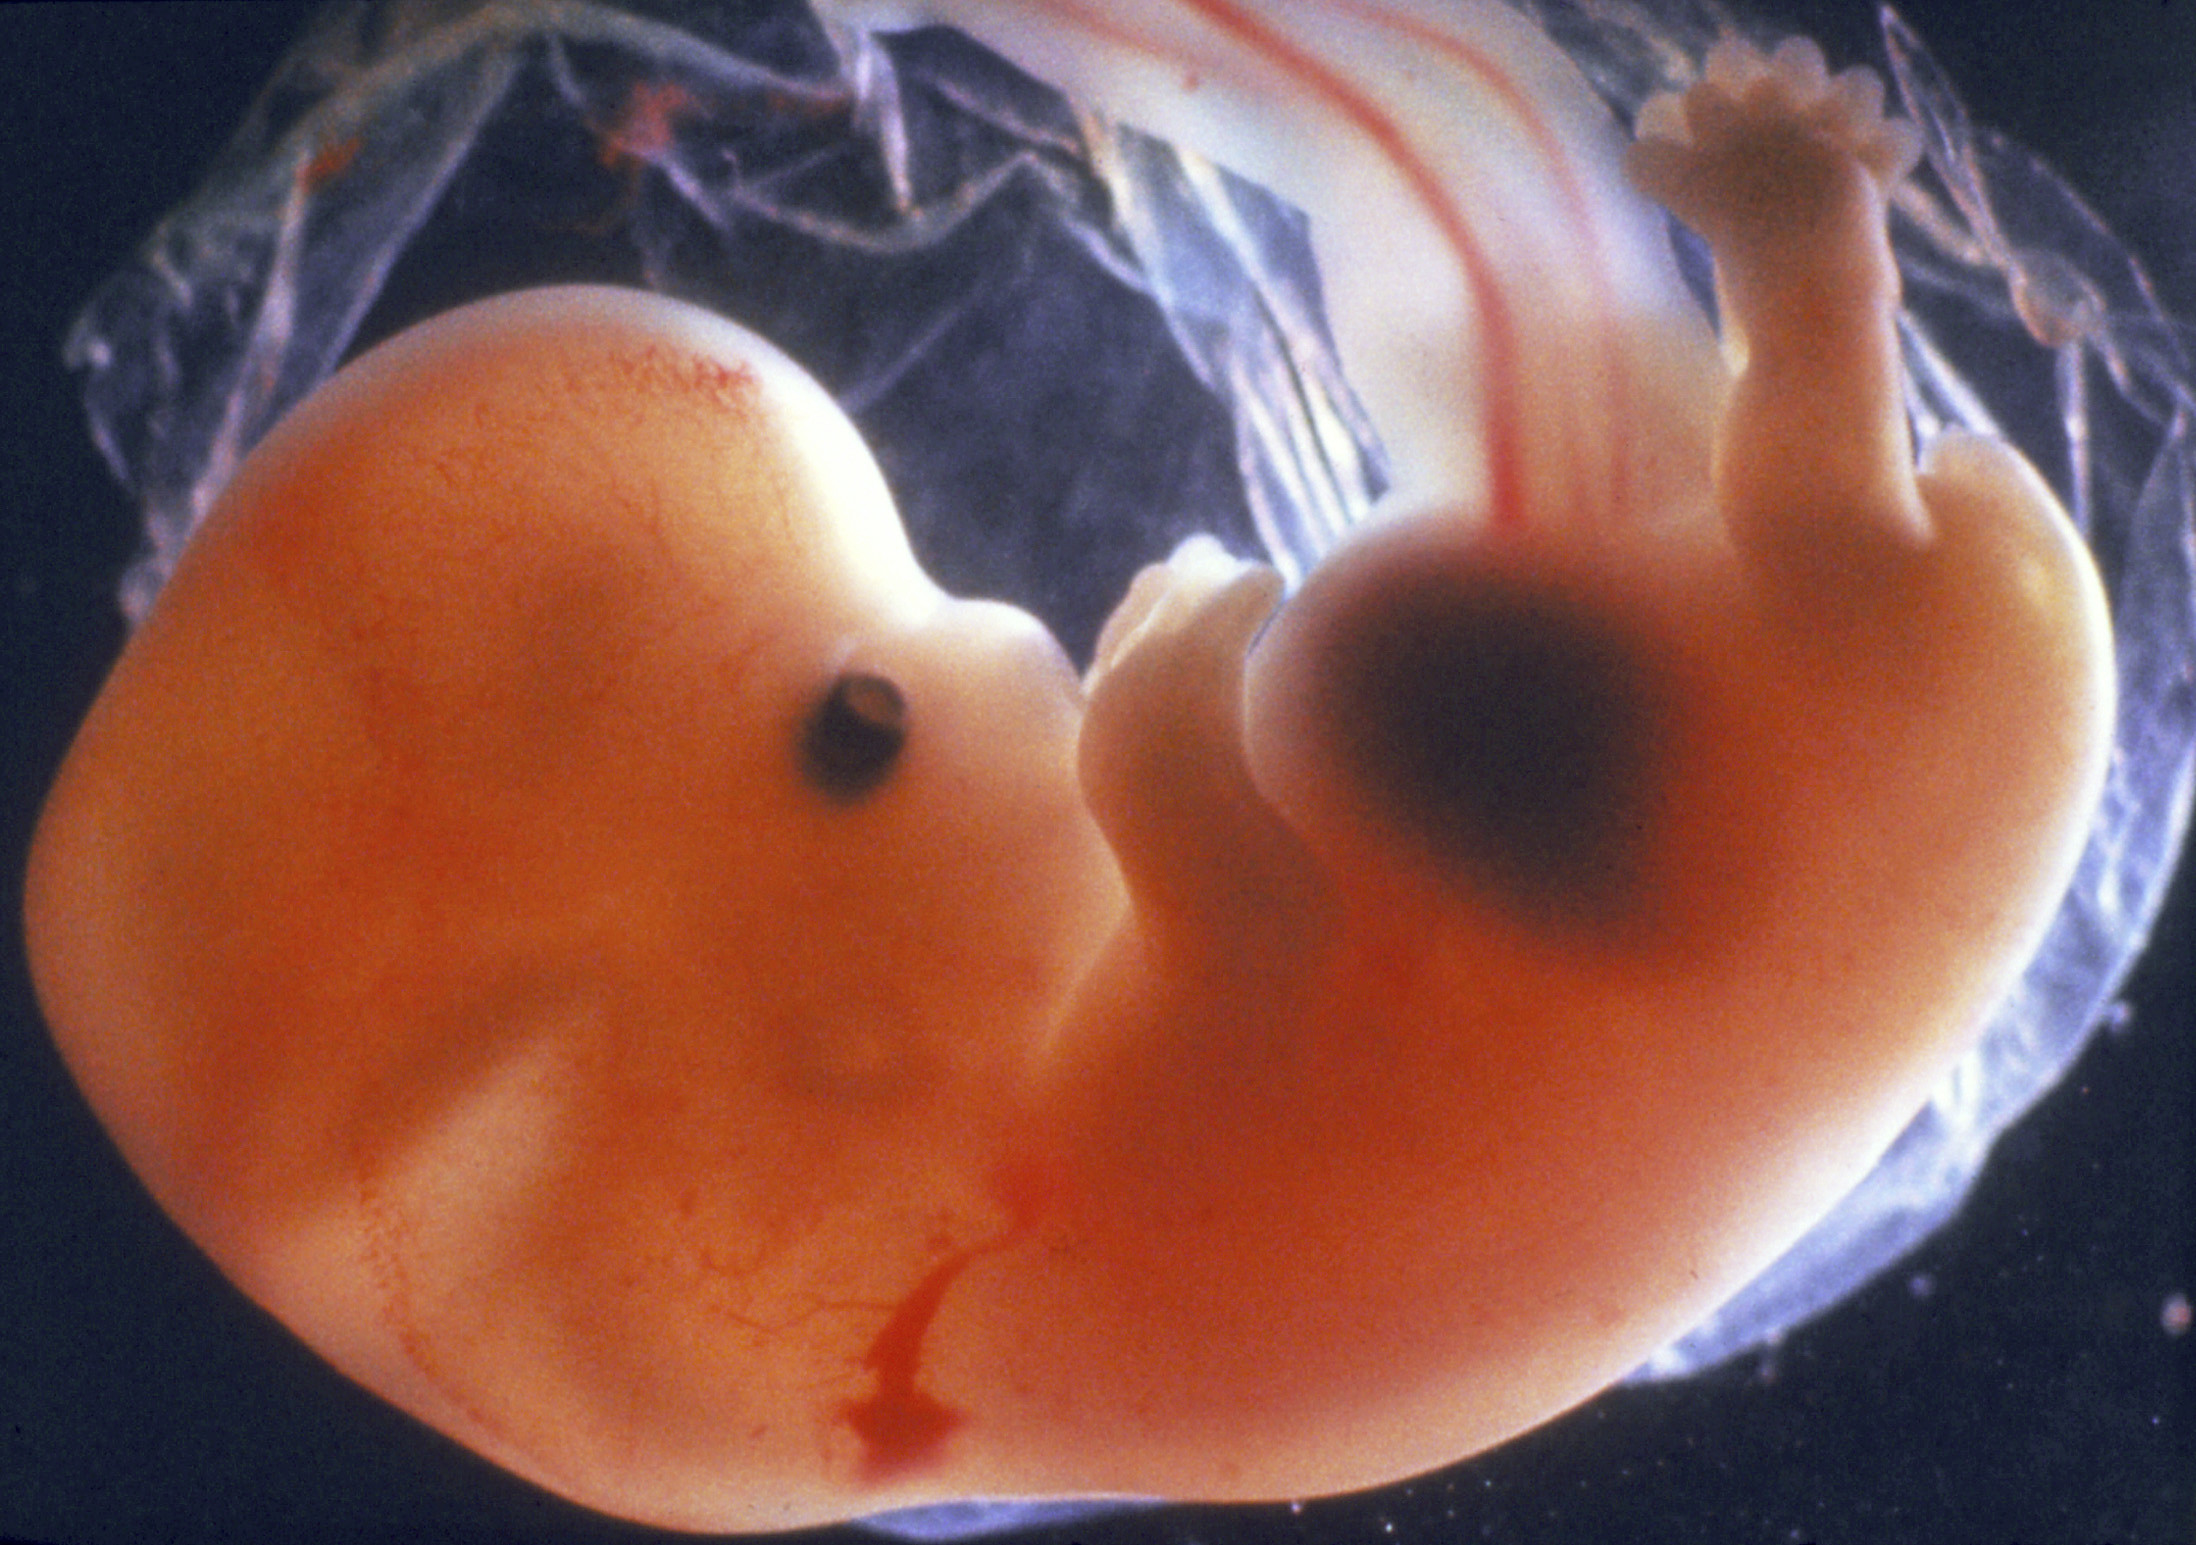

Развитие эмбриона: Что происходит на 3 неделе беременности

Раздел: Фотопанорама